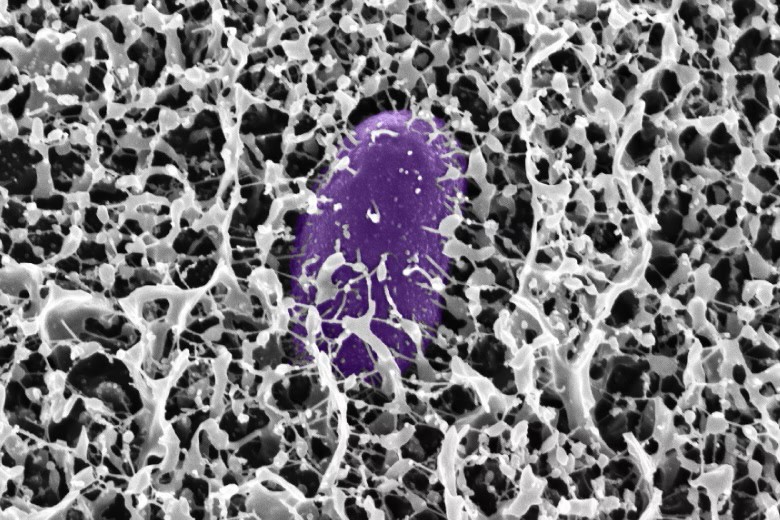

Researchers at MIT have made a significant advancement in gene therapy, offering new hope for treating genetic diseases caused by a missing or defective gene. For years, scientists have pursued gene therapy as a potential cure for a range of monogenic diseases, where a single defective gene causes the disorder. However, the challenge has always been controlling how much of the therapeutic gene is expressed in target cells—too little expression means the therapy won’t work, while too much could result in harmful side effects.

In a study published in Cell Systems, MIT engineers have developed a system that delivers precise control over gene expression levels. Their method, called the ComMAND circuit (Compact microRNA-mediated Attenuator of Noise and Dosage), uses a novel feedback mechanism to regulate the amount of gene product produced in cells. This innovation could pave the way for safer, more effective gene therapies for conditions like Fragile X syndrome and Friedreich’s ataxia.

Led by MIT graduate student Kasey Love and senior author Katie Galloway, a professor in biomedical and chemical engineering, the research focuses on a special type of genetic control circuit known as an incoherent feedforward loop (IFFL). The circuit works by simultaneously activating both the target gene and a microRNA that suppresses the gene’s expression. This self-regulation helps keep gene expression at optimal levels—enough to be effective, but not so much as to cause toxicity.

“Gene supplementation can solve many monogenic disorders if we can control the therapy precisely,” explains Galloway. The team demonstrated this technique by targeting genes associated with Fragile X syndrome and Friedreich’s ataxia—both of which result in neurological and developmental issues. They successfully fine-tuned gene expression to levels that were eight times higher than normal, avoiding the excessive expression seen in earlier gene therapies that could have harmful consequences.

The key advantage of the ComMAND circuit is its compact design, which allows it to be delivered using common viral vectors like lentiviruses or adeno-associated viruses—the same delivery systems used in current gene therapy treatments. This simplicity improves the manufacturability and scalability of the therapy.

While the researchers have demonstrated success in human cells, they acknowledge that further tests in animal models are needed to fine-tune the system for clinical use. They hope this technology could eventually benefit patients with a range of genetic disorders, including muscular dystrophy, spinal muscular atrophy, and Rett syndrome.